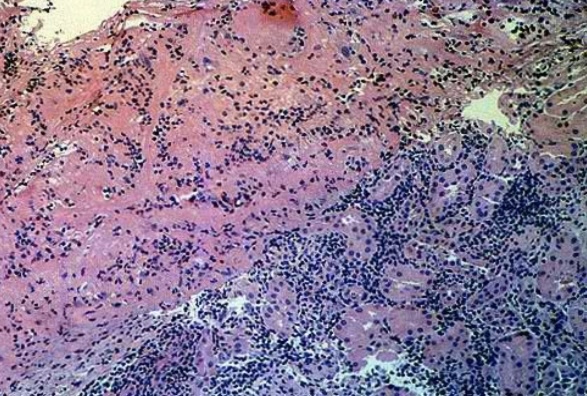

Liquefactive necrosis